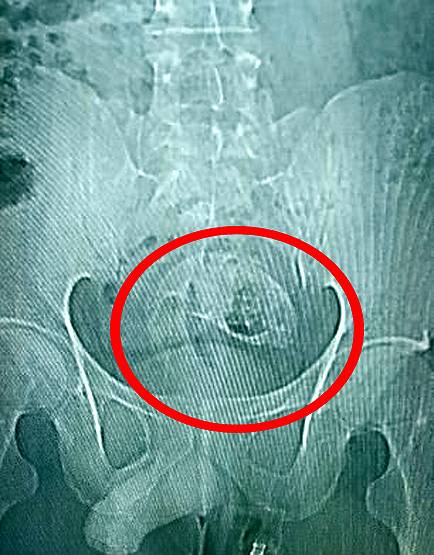

हुआ यूं कि चीन के गुआंगडोंग प्रांत के झाओक्विंग में एक 30 वर्षीय युवक ने बताया कि वह गलती से एक मछली के ऊपर बैठ गया. ये मछली उसे मलाशय (Rectum) से होते हुए पेट तक पहुंच गई. इस दौरान मछली ने बड़ी आंत में काफी घाव कर दिया. बड़ी आंत में फंसी मछली का एक्स-रे.

जब उस युवक को पेट में दर्द होने लगा और वह खुद से मछली नहीं निकाल पाया तो वह झाओक्विंग फर्स्ट पीपुल्स अस्पताल पहुंचा. उसने डॉक्टरों को ये बात बताई कि वह गलती से मछली के ऊपर बैठ गया था. मछली गुदा द्वार से शरीर के अंदर पहुंच गई. बड़ी आंत में फंसी मछली का एक्स-रे.

डेलीमेल वेबसाइट की खबर के अनुसार डॉक्टरों ने तत्काल एक्स-रे निकाला. उसमें मछली बड़ी आंत में फंसी हुई दिखाई दे रही थी. इसके बाद डॉक्टरों ने पहले तो युवक के मलाशय से मछली निकालने की कोशिश की लेकिन मछली काफी बड़ी थी, इसलिए पेट का ऑपरेशन किया गया.